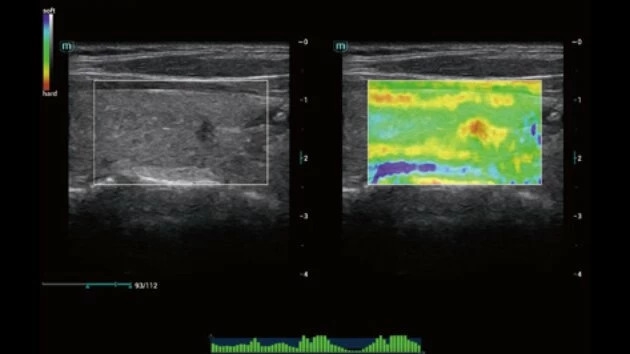

- Высокое разрешение изображений для точной диагностики

- Широкий спектр клинических исследований

- Расширенные возможности визуализации различных органов и тканей